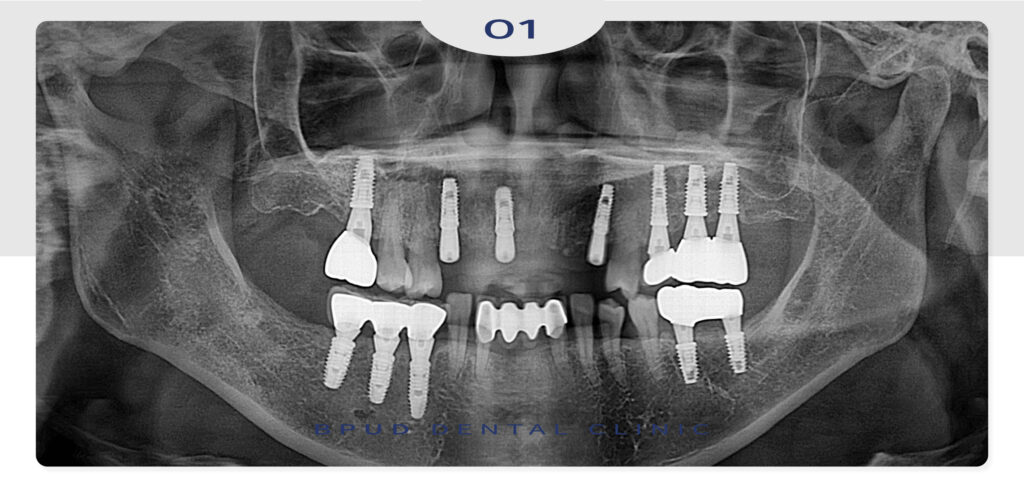

오늘은 잇몸이 붓고 흔들리는

비심미적인 앞니를 발치하고

임플란트를 식립하여 심미적으로

보철을 완성하신 환자분을 소개해

드리도록 하겠습니다.

환자분께서는 부평치과에서 다른 치료를

받았던 분으로 최근에 위쪽 앞니가 붓고

흔들리며 통증이 느껴지신다고 말씀하시며

너무 이쁘지 않다고 말씀해 주셨는데요.

25.09.13

위쪽 앞니 중 씌워져 있던 4개와

양 옆의 상태가 좋지 않았던 송곳니까지

총 6개를 발치하고 비용적인 부분을 고려해

3개의 임플란트를 식립하기로 하였습니다.

더불어 골흡수가 심하게 진행된 부위는

뼈이식을 함께 진행하였는데요.